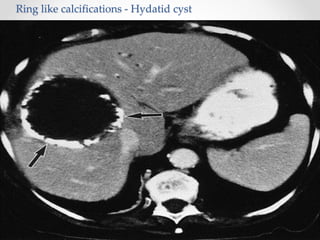

Hydatid Cyst

• Hydatid disease is due to infection by the tapeworm

Echinococcus granulosus in its larval or cyst stage.

• 70 % of hydatid cysts found in the liver , others found in lung ,

brain or bone.

• Hydatid cysts commonly involve the right lobe of the liver,

usually the anterior-inferior or posterior-inferior segments .

Eosinophilia is seen in approximately 30% of infected patients.

Ultrasonography and CT scanning of the abdomen are both quite

sensitive for detecting hydatid cysts.

Ring like calcifications - Hydatid cyst